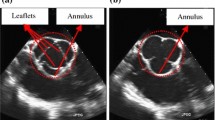

For planning and guidance of minimally invasive mitral valve repair procedures, 3D+t transesophageal echocardiography (TEE) sequences are acquired before and after the intervention. The valve is then visually and quantitatively assessed in selected phases. To enable a quantitative assessment of valve geometry and pathological properties in all heart phases, as well as the changes achieved through surgery, we aim to provide a new 4D segmentation method.

We propose a tracking-based approach combining gradient vector flow (GVF) and position-based dynamics (PBD). An open-state surface model of the valve is propagated through time to the closed state, attracted by the GVF field of the leaflet area. The PBD method ensures topological consistency during deformation. For evaluation, one expert in cardiac surgery annotated the closed-state leaflets in 10 TEE sequences of patients with normal and abnormal mitral valves, and defined the corresponding open-state models.

Our approach enables to segment the mitral valve in 4D TEE image data with normal and pathological valve closing behavior. With this method, in addition to the quantification of the remaining orifice area, shape and dimensions of the coaptation zone can be analyzed and considered for planning and surgical result assessment.